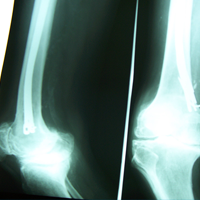

Case:19 Percutaneous fixation with Implants

A male patient, aged 78 years had been diagnosed to have a closed Pott’s fracture Left Ankle. He was treated operatively with Percutaneous fixation with Implants.

Pre-Operative

Post-Operative